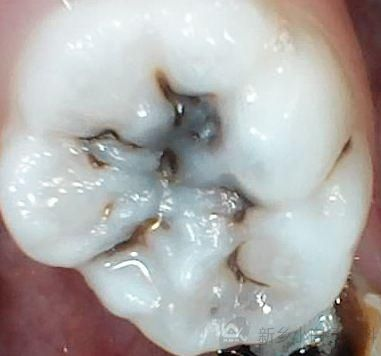

患者尚某某,女,7岁。家长发现患儿牙面发黑,影响美观,于2015年2月23日来我院就诊,检查发现75深龋。治疗方案:75护充。治疗过程:3%双氧水含漱一分钟,去腐备洞,隔湿干燥,Z250充填,调合。2小时后治疗结束。

治疗前